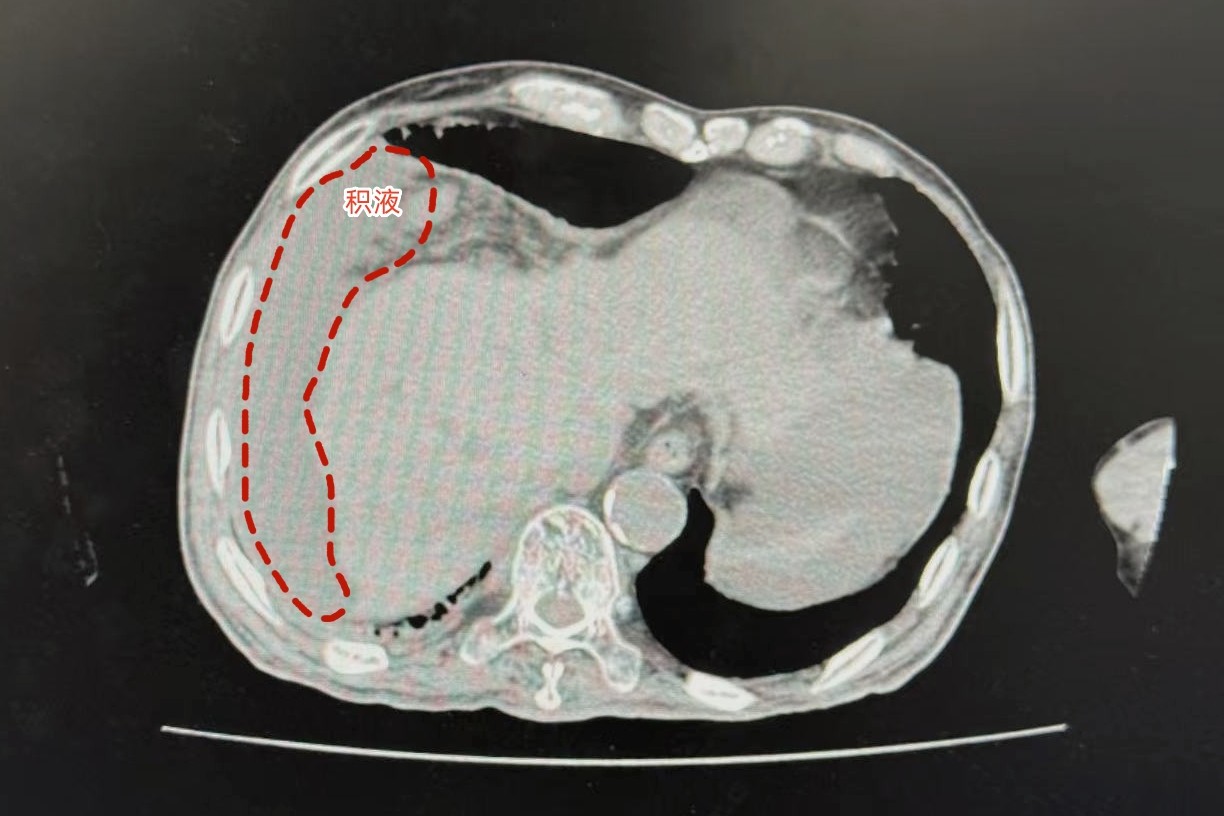

3月初,62岁的黄先生来到江苏省中西医结合医院消化科副主任中医师徐婷婷的门诊,比人先进入诊室的,是他像气球一样鼓起来的肚子。“医生,这段时间我腹胀得厉害,双腿也肿,排尿还特别少,这是怎么了?”经过详细问诊,徐婷婷结合病史予以B超检查,很快结果提示:腹盆腔积液、右侧胸腔少量积液,肝硬化,并伴有肝硬化腹水。于是将其收治入院。

面对老黄,徐主任并不陌生,5年前,正是她为黄先生确诊了酒精性脂肪肝。“怎么会发展得这么快?”面对徐婷婷的问询,黄先生坦言,虽然5年前查出了酒精性脂肪肝,有努力控制饮酒量,但自己从20多岁就开始喝酒,实在难以坚持,现在每天依然要喝半斤白酒,平日里也没有按时服药,更没有及时记录排尿量和复诊,现在很是懊悔。为尽快控制病情,徐婷婷采取抽腹水、加强营养支持、补充白蛋白等一系列保肝对症治疗,同时予以科室特色中药代泡饮“护肝降脂茶”缓解炎症。